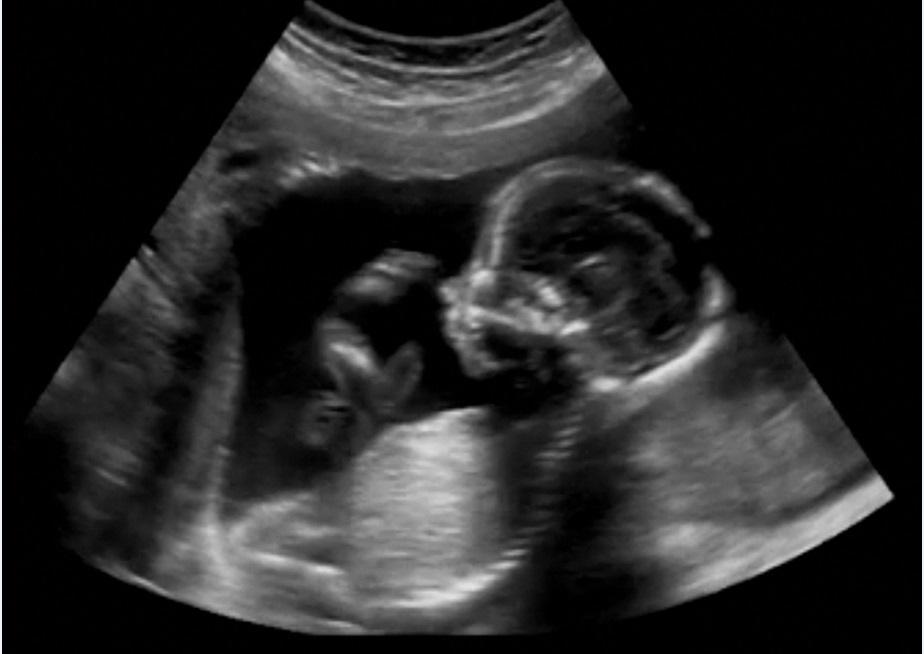

Just in time for the annual March for Life, which took place on Friday, Senator Paul introduced new legislation that would ensure that pre-born children are accorded the same rights enjoyed by every other human in our country.

U.S. Senator Rand Paul today introduced the Life at Conception Act. The legislation would implement equal protection under the 14th Amendment for the right to life of each born and unborn human. The Life at Conception Act does not amend or interpret the Constitution, but simply relies on the 14th Amendment, which specifically authorizes Congress to enforce its provisions.

“As thousands of Americans prepare to participate in the annual March for Life, it is time for Congress to recognize the right to life is guaranteed to all Americans in the Declaration of Independence, and it is the constitutional duty of all members of Congress to ensure this belief is upheld. The Life at Conception Act legislatively declares what most Americans believe and what science has long known – that human life begins at the moment of conception, and therefore, is entitled to legal protection from that point forward. Only when America chooses, remembers, and restores her respect for life will we rediscover our moral bearings and truly find our way.”